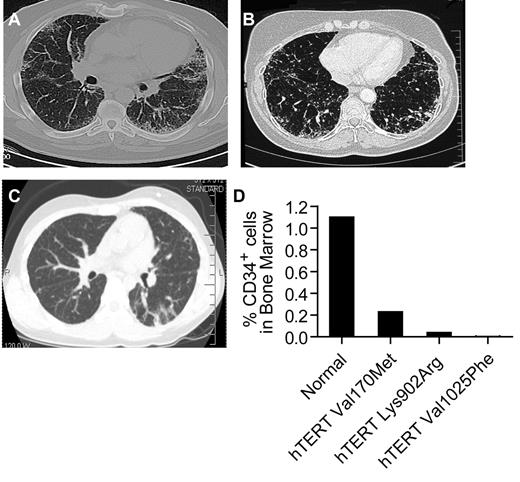

Ten consecutive individuals fulfilled the study criteria; 6 cases first came to clinical attention for symptoms related to AA, and 4 with symptoms related to idiopathic interstitial lung disease (Table 1). Six of the 10 individuals were subsequently diagnosed with a second feature (Table 1). Representative computed axial tomography (CAT) scan images and bone marrow studies are shown (Figure 1A-D). The mean age at first diagnosis for patients who presented with AA was significantly younger than those with pulmonary fibrosis: 14 years (range 9-21) vs 51 years (range 44-61; P < .001 by Student t test). For all 10 cases, there was at least one other first-degree relative who had bone marrow failure or pulmonary disease (Figure 2A). All of the pedigrees showed an inheritance pattern consistent with autosomal dominant transmission. In 8 of 10 families, we observed heterogeneity of phenotypes across generations. Specifically, within each of these 8 families, older generations first manifested with pulmonary fibrosis, and subsequent generations with bone marrow failure (Figure 2A). In 2 families, there was a case of cryptogenic liver cirrhosis that led to premature mortality. Two of the 10 probands were children with AA who subsequently developed progressive pulmonary disease within 3 years after myeloablative bone marrow transplantation. In both cases, reevaluation of the family history revealed cases of AA and pulmonary fibrosis in relatives. Two patients with pulmonary fibrosis, although they came to medical attention with respiratory symptoms, were later noted to have significant cytopenias, and one patient required prolonged transfusion support while on myelosuppressive drugs. None of the probands we examined had any of the classic features of DC or the less frequent features such as epiphora, but the majority reported a history of premature hair graying before age 25 (7 of 10, mean 17 years, range 6-23).

Evidence of both pulmonary fibrosis and bone marrow failure in individuals with mutant telomerase genes. (A-B) Representative CAT scan images showing typical peripheral honeycombing pattern in 2 individuals with idiopathic pulmonary fibrosis and pancytopenia. Both individuals had biopsy confirmation of the usual interstitial pneumonia. The scans are from individuals in families 2 and 6. (C) CAT scan image of the proband of family 7, who developed pulmonary fibrosis after bone marrow transplantation for AA. Biopsy confirmed nonspecific interstitial pneumonia. (D) For the 3 individuals with images shown, the percentage of bone marrow CD34+ cells by flow cytometry was decreased in the setting of pancytopenia, macrocytosis, and hypocellular/aplastic marrow. The 95% confidence interval for CD34+ percentage is 0.4%-1.8%.